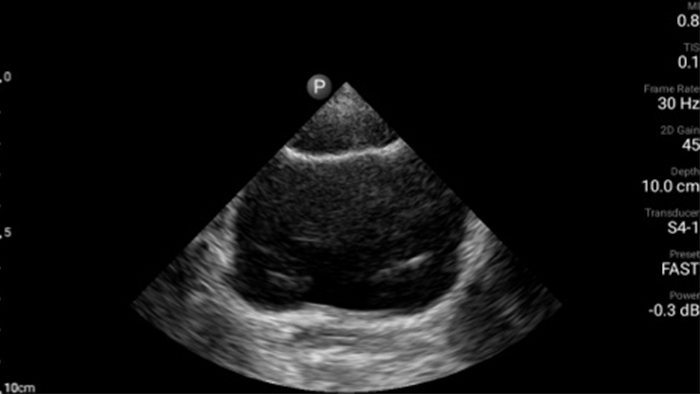

Get the full picture with clear whole-body imagery for a fast, accurate response during an emergency.

• 4 to 1 MHz extended operating frequency range • 2D, color Doppler, M-mode, advanced XRES and multivariate harmonic imaging • High-resolution imaging for abdominal and cardiac applications: Cardiac, OB/GYN, Lung, Abdomen and FAST imaging preset optimizations Lumify aids life-saving technology in prehospital setting

Focused Assessment with Sonography in Trauma (FAST) exam